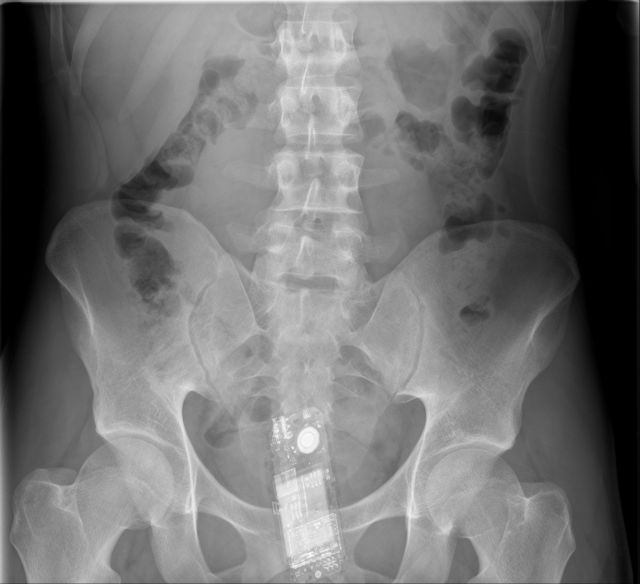

Cell phone